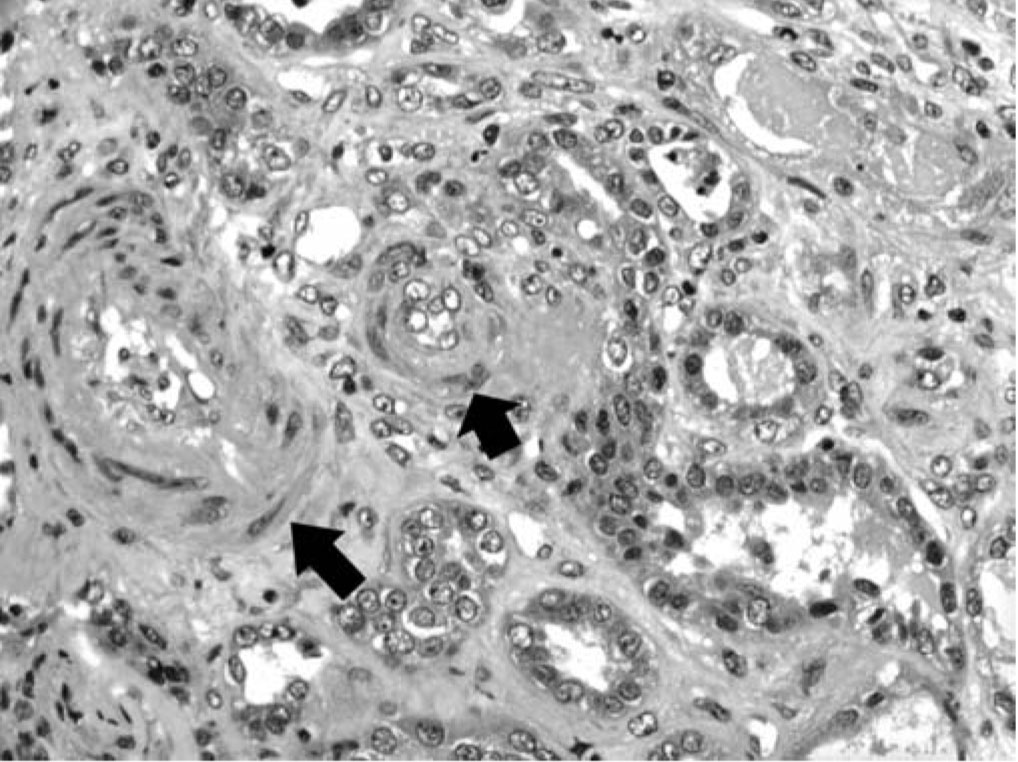

Renal biopsy was done (figure) and a diagnostic test was done

In the present case, renal, cardiac and hepatic-biliary involvement was present in the 1st week of the disease, acute TMA in the renal tissue was demonstrated, and the presence of aPL was repeatedly documented.